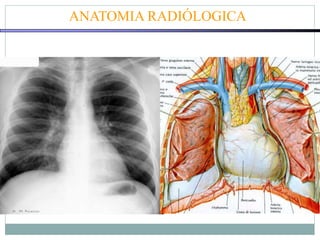

ANATOMIA RADIÓLOGICA